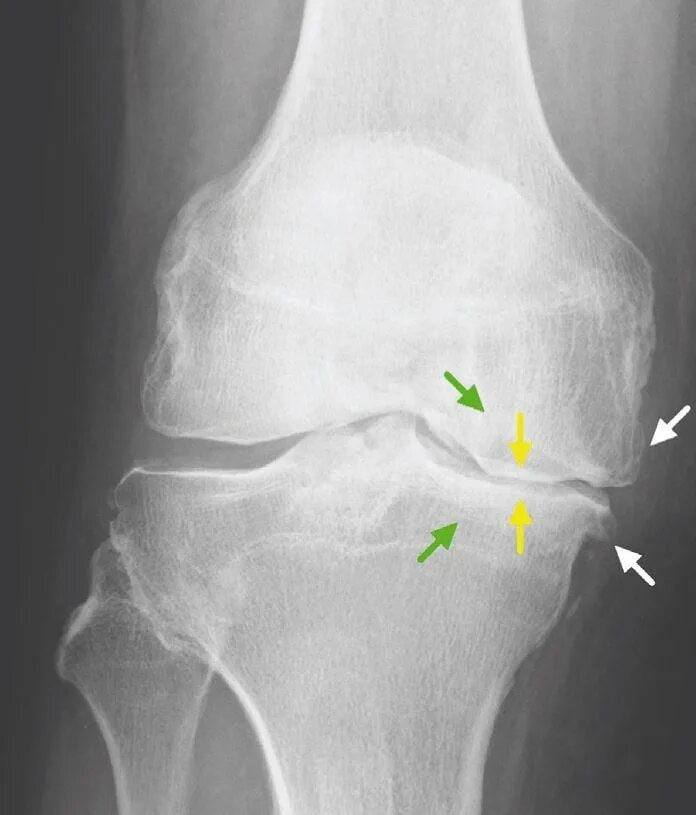

Гонартроз коленного сустава мкб 10